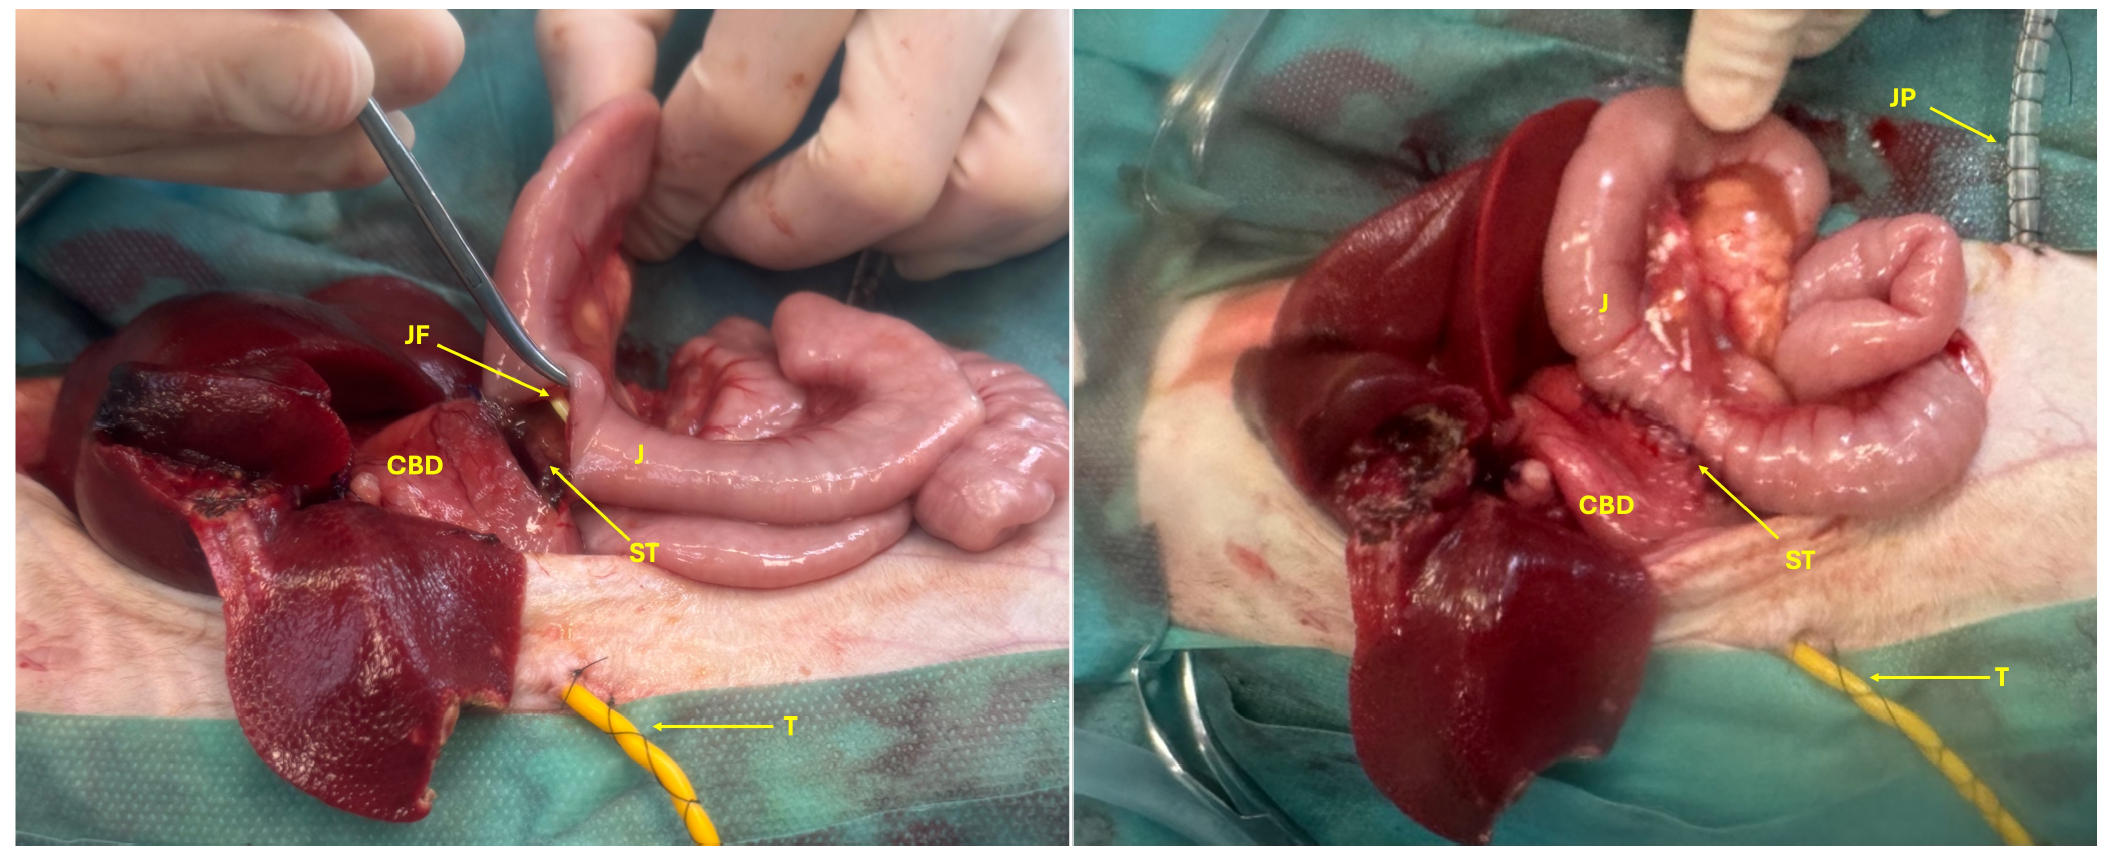

通过食管插管引入空肠喂养管,并通过十二指肠切开术将其推进至空肠。采用4-0缝线以单层连续缝合模式将扩张的胆总管与空肠进行胆肠吻合,完成胆道空肠吻合术(下图)。更换手套和器械后,对腹腔进行冲洗。放置了腹腔引流管,并进行了常规腹腔关闭。

↑ 胆总管(CBD)与空肠(J)之间的胆肠吻合术(ST),带有空肠喂养管(JF)、胆道造口管(T)和腹腔引流管(JP)。